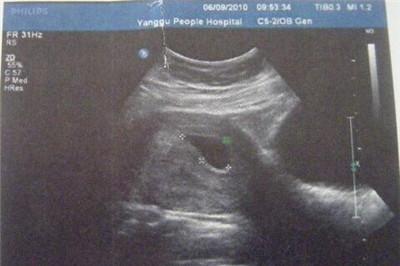

孕囊生男生女早知道:看孕囊b超图

生男生女早知道可以通过看孕囊b超图:

1、首先数据不能超过8周的,40多天是最合适的。然后就是要有3个数据的,没有3个数据的,一律不能判断,因为每个B超师获取孕囊的方位不一样。

2、有3个数据的,是最好判断的,两个数据差不多,第三个数据比前两个小一倍,那肯定是儿子,如果成递减数据就是女儿。

孕囊形状看胎儿性别:

有人认为,孕囊形状可以看出胎儿是男是女。一般说来,如果孕囊的形状像茄子,或者是呈长条状的,则怀上男宝宝的可能性大;而如果孕囊是椭圆形或圆形的,那么很可能就是个女宝宝了。